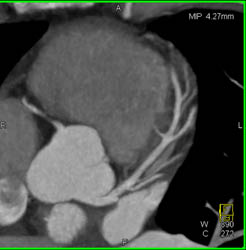

Dilated Origin of Right Main Coronary Artery